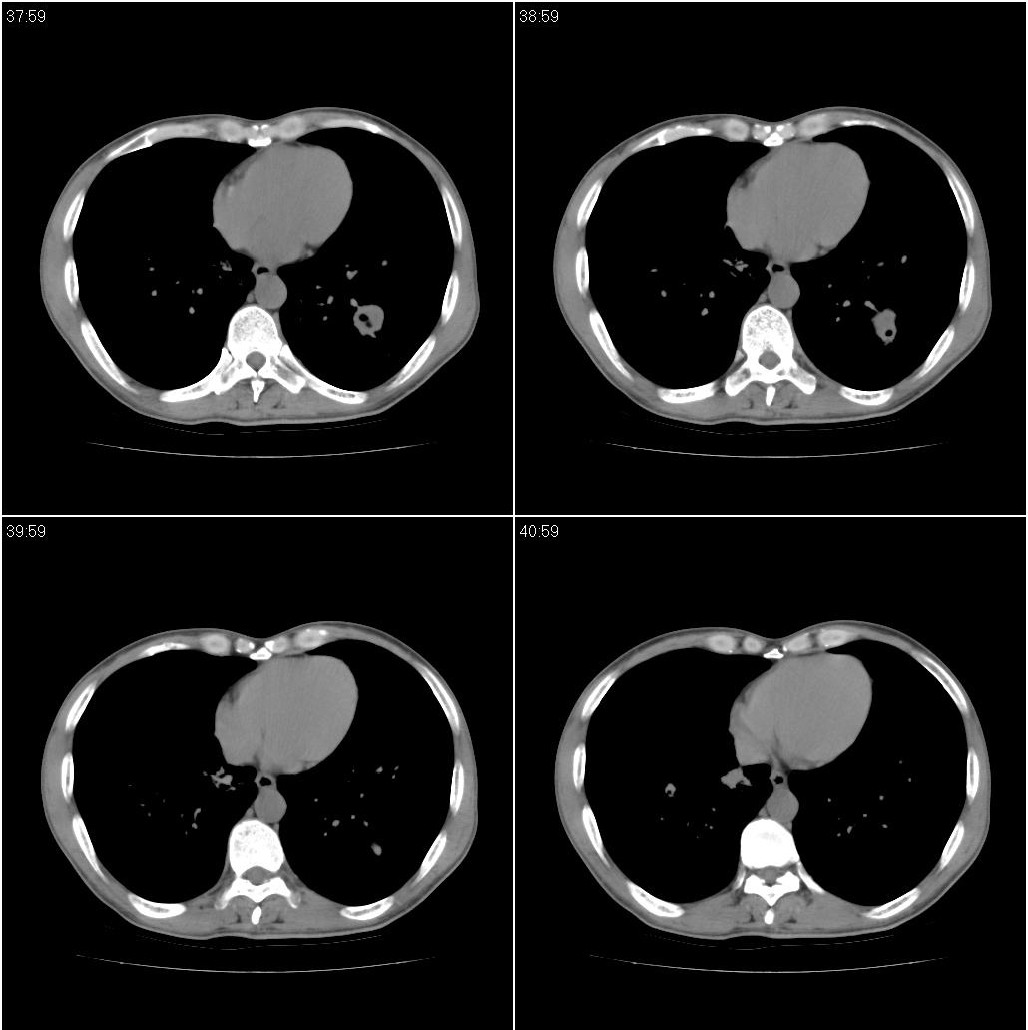

标题: CT23980:男性,47岁。近来咳痰、咳血,血沉增快(40左右),

男性,47岁。近来咳痰、咳血,血沉增快(40左右),痰中未检出结核杆菌。

两肺继发性肺结核并多发性结核球形成,部分病灶内空洞形成。